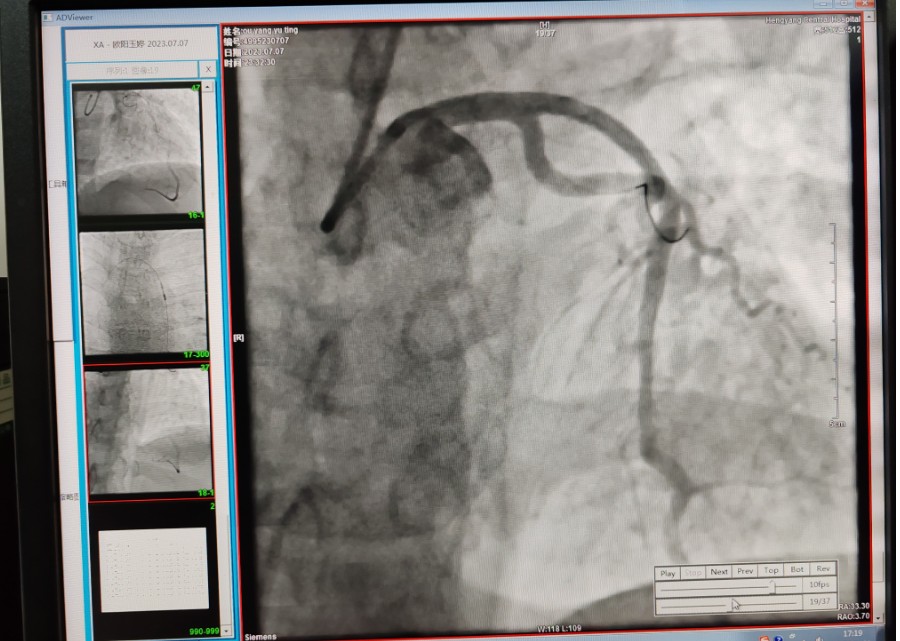

22:29分患者經(jīng)院內(nèi)綠色通道送達(dá)導(dǎo)管室,手術(shù)由雷剛副主任醫(yī)師主刀,楊繼賀副主任醫(yī)師為第一助手,介入技師及護(hù)士密切配合,聞?dòng)嵍鴣淼内w慶禧主任醫(yī)師坐鎮(zhèn)協(xié)調(diào)指揮。22:37分手術(shù)開始,冠脈造影顯示心臟上最重要的一條冠狀動(dòng)脈-前降支開口齊頭閉塞,血管粗大且血栓高負(fù)荷,非??简?yàn)介入術(shù)者的手術(shù)能力,一旦發(fā)生冠脈無復(fù)流或操作不慎血栓帶入回旋支導(dǎo)致循環(huán)崩潰,病人幾乎無生還希望;此時(shí),患者手術(shù)臺上仍持續(xù)胸痛,且血氧飽和度在高流量吸氧狀態(tài)下不到80%,雷剛副主任醫(yī)師一方面指揮鎮(zhèn)靜鎮(zhèn)痛及抗心衰治療,一方面緊急啟用IABP(主動(dòng)脈球囊反搏),然后精細(xì)操控細(xì)如發(fā)絲的介入導(dǎo)絲迅速通過病變,并予冠脈球囊擴(kuò)張、冠脈內(nèi)溶栓、抗痙攣藥物使用、植入冠脈支架,最終成功開通“罪犯”血管,且無手術(shù)并發(fā)癥發(fā)生,整個(gè)過程張弛有度、快慢結(jié)合、一氣呵成?;颊咝g(shù)后胸痛明顯好轉(zhuǎn),血氧飽和度上升至96%,術(shù)后1天轉(zhuǎn)出監(jiān)護(hù)病房,第3天拔出IABP,目前已康復(fù)出院。